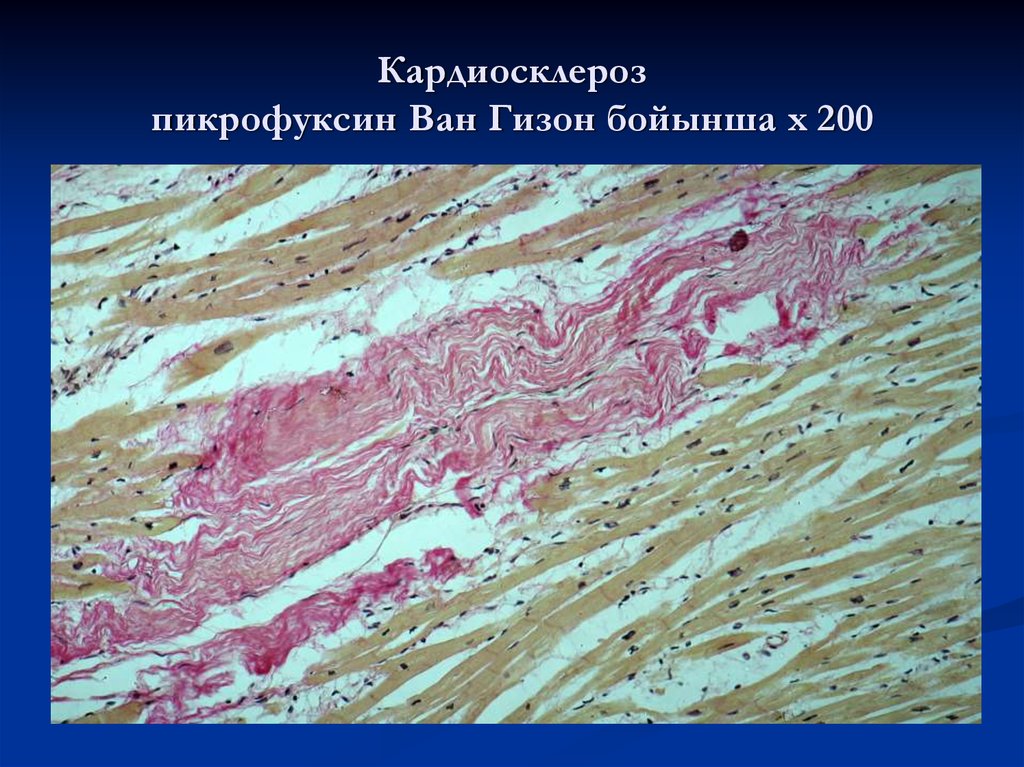

Межуточный миокардит: гистологические исследования